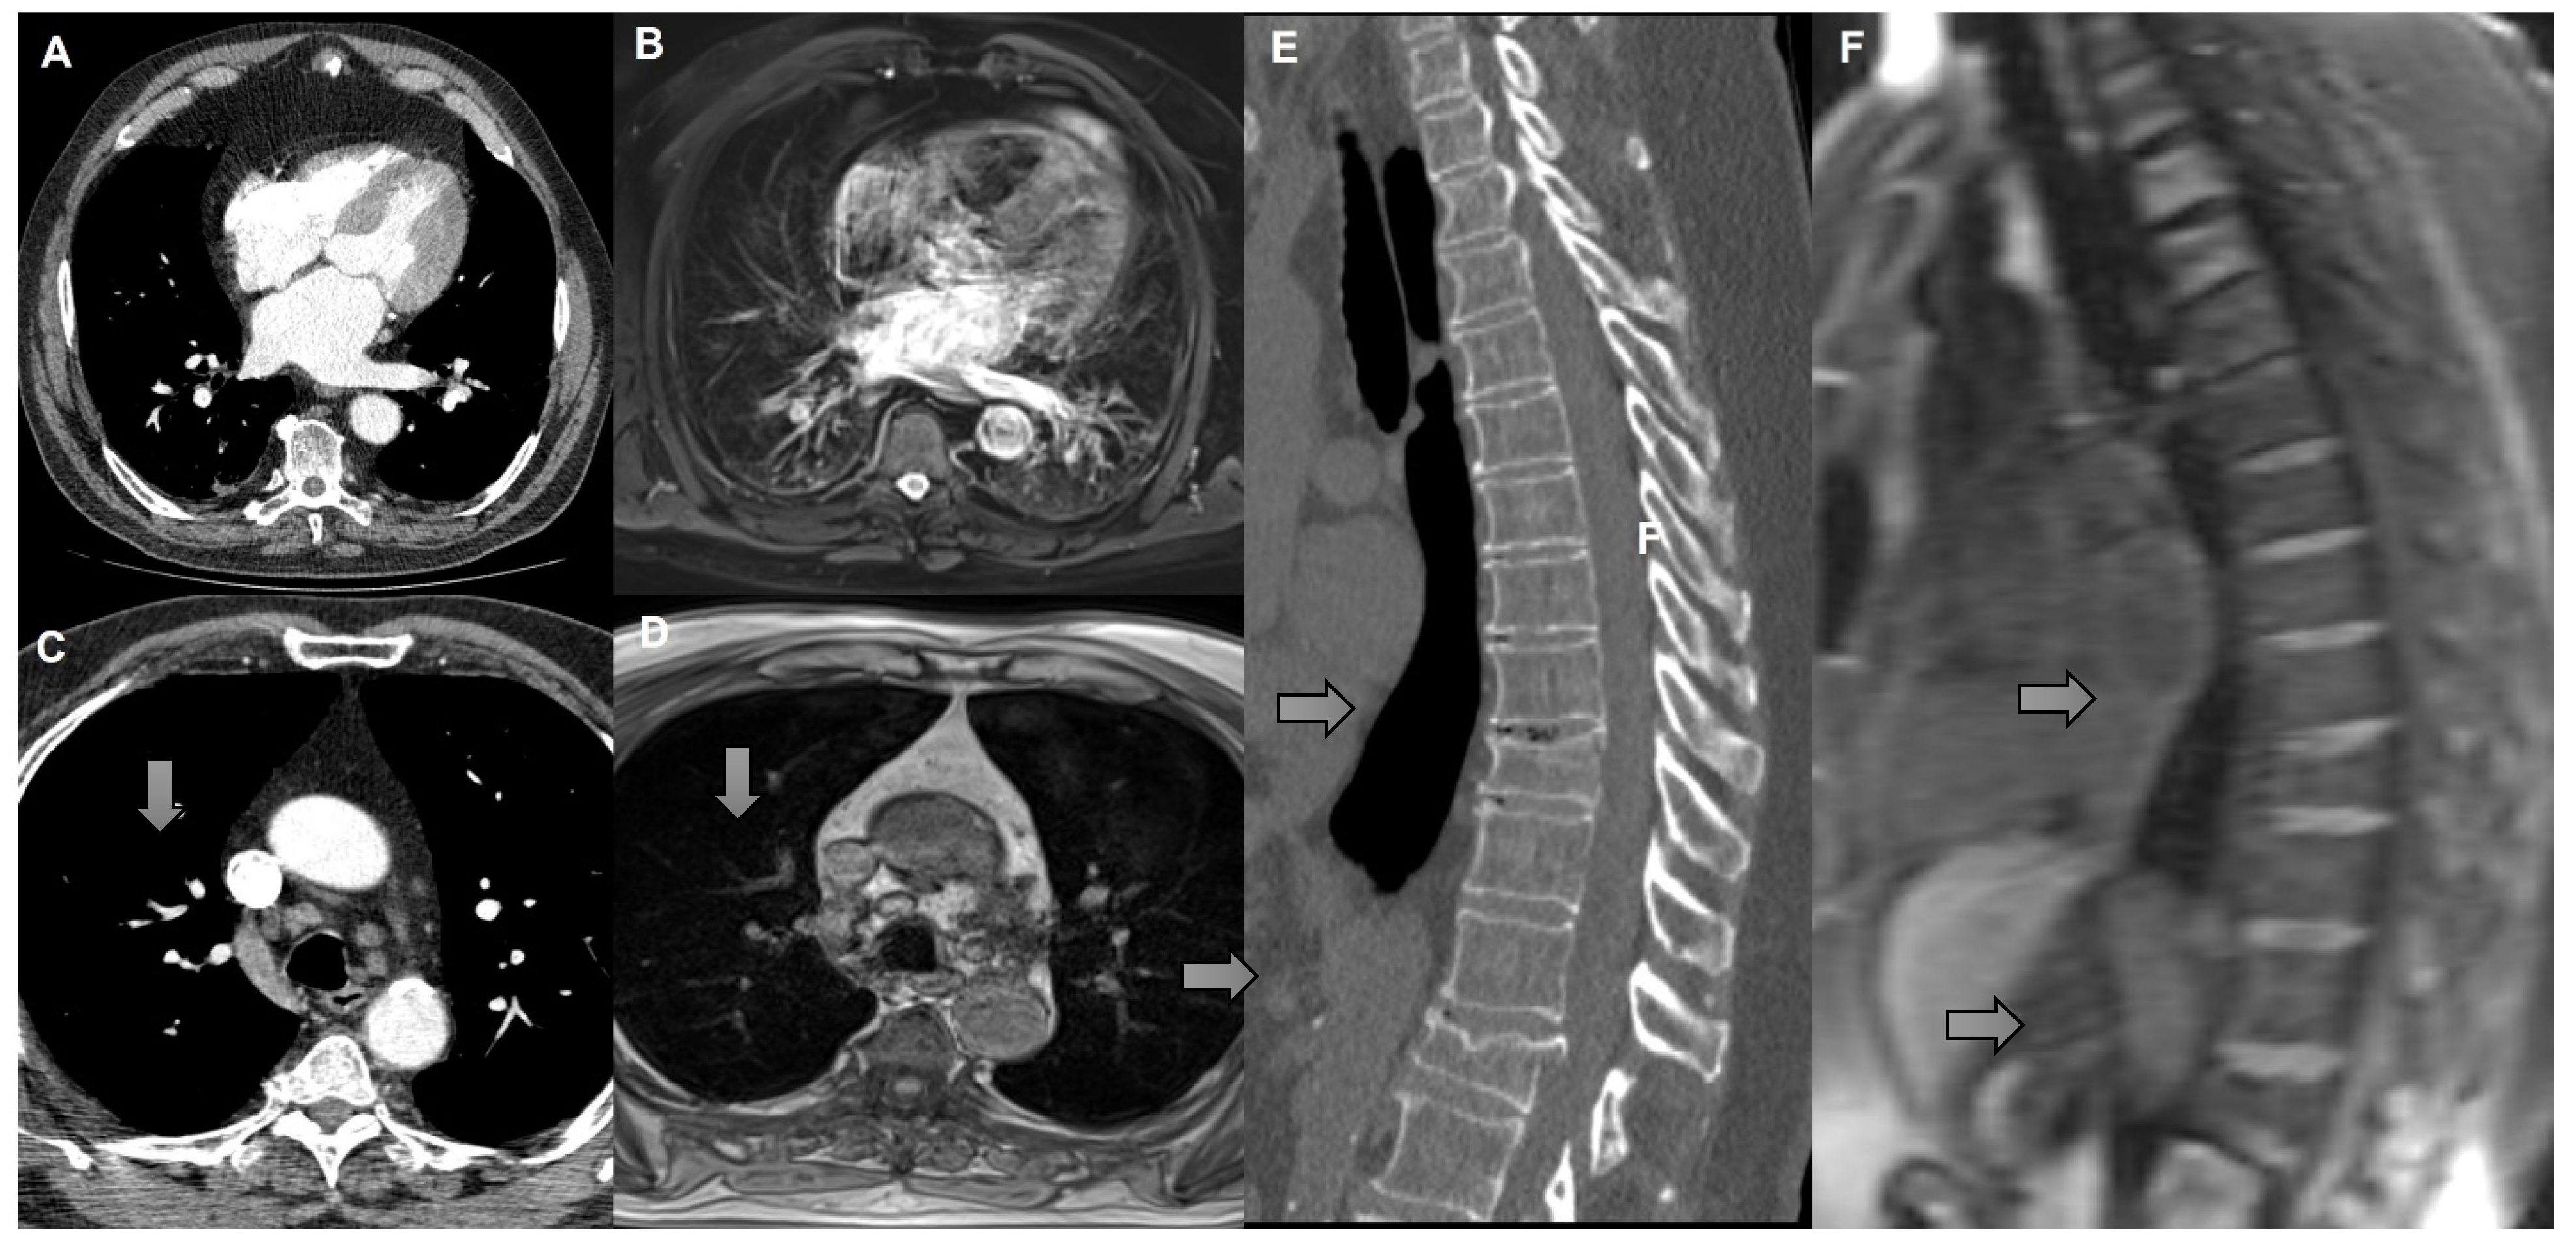

3.2. MR Findings